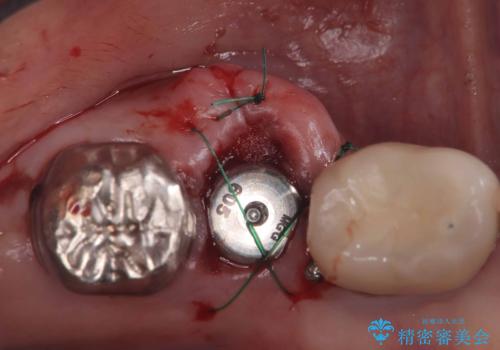

根管の中が空洞のままで被せ物と歯のきわも合っておらず適合が悪い状態でした。根尖部付近にはパーフォレーションリペア修復の痕がありました。バイオシーシーラーを使用しシングルポイント法で充填しました。空洞があると細菌が増える環境になってしまうので、根管治療からやり直し、緊密に充填しました。被せ物の見た目も大変満足していただけました。